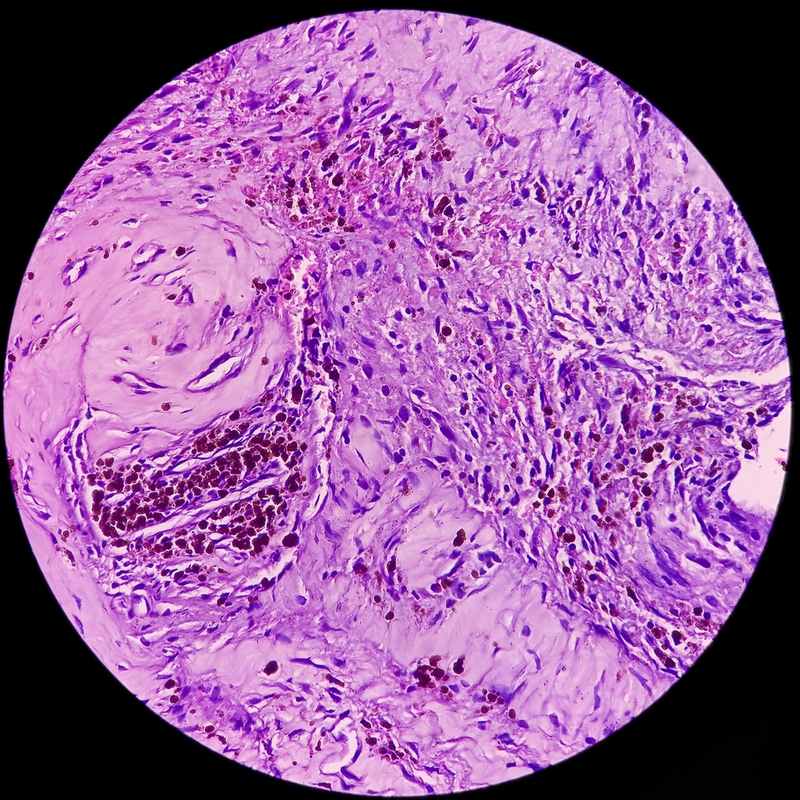

Facial nerve tumor

Facial nerve tumor 114 photos